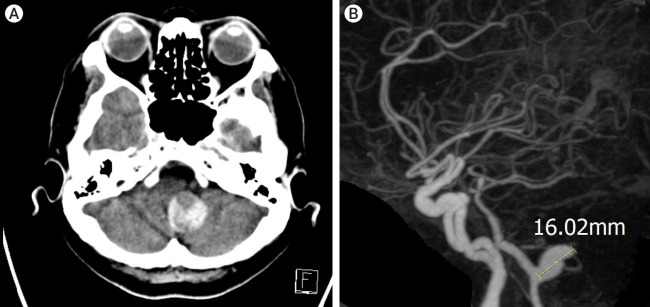

纤维肌发育不良(FMD)是一种主要影响女性的非炎症性动脉疾病。多项研究表明,在经历颈动脉或椎动脉夹层(VAD)的患者中,FMD的患病率增加。本病例报告介绍了一名57岁的女性,她表现出头痛,并被诊断为部分血栓形成的椎动脉巨大动脉瘤。该动脉瘤用分流器和线圈成功治疗,但两周后发现新发的椎动脉破裂,导致内陷。本病例报告强调了对疑似FMD患者的夹层和动脉瘤治疗的认识和理解的必要性。

Fibromuscular dysplasia (FMD) is a noninflammatory arterial diseases that affects predominantly women. Multiple studies have demonstrated an increased prevalence of FMD in patients who experience carotid or vertebral artery dissection (VAD). This case report presents a 57-year-old female who presented with a headache and was diagnosed with partially thrombosed giant aneurysm of vertebral artery. This aneurysm was successfully treated with flow-diverter and coil, but new onset rupture of vertebral artery was detected two weeks later, leading to internal trapping. This case report underscores the need for awareness and understanding of treatment of dissection and aneurysm in patient who is suspected FMD.